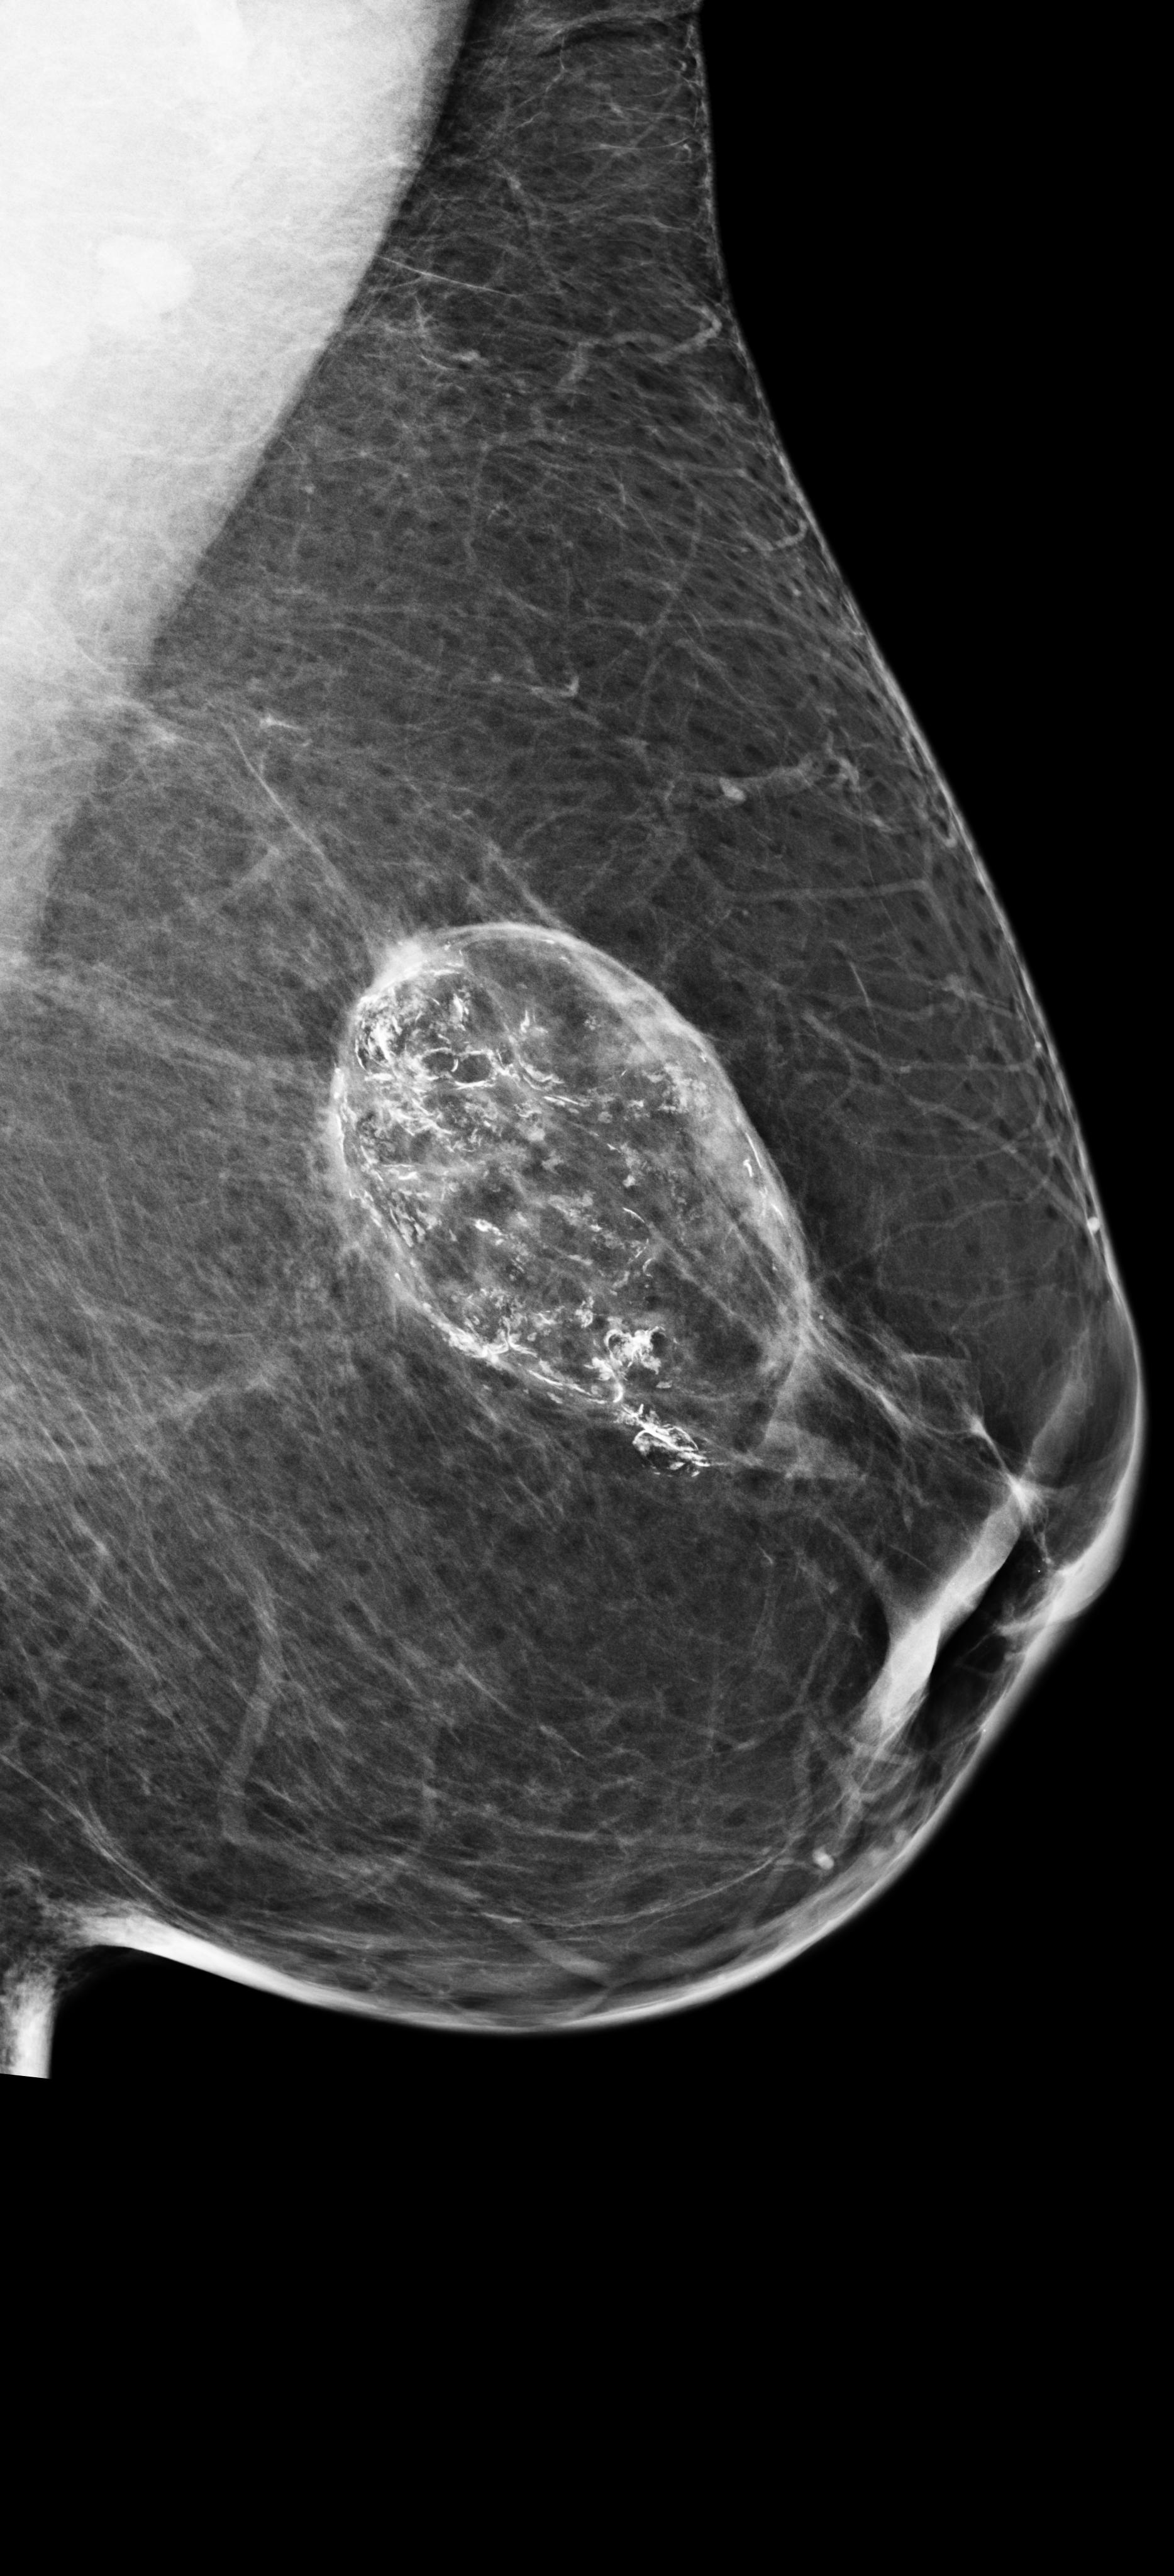

The results from all three models are shown in \tablereftab:example. AlignLocalCompare performs better for malignant prediction than the single-exam baseline and GlobalCompare, in both the biopsied and screening populations. We do not observe improvement for benign category–we speculate that this is because our model learns to focus on regions with significant changes, but not many changes accompany benign findings. In \figurereffig:exams, we visualize a few cases where the AlignLocalCompare is more confident in its prediction than the single-exam baseline Wu et al. (2019a). For \figurereffig:exams(a), we observe that the malignant region did not exist in the prior exam. For \figurereffig:exams(b), we observe that the bright spot at the center already existed in the prior exam, and the model can be more sure that it is not malignant.

[\capbeside\thisfloatsetupcapbesideposition=left,top,capbesidewidth=6cm]figure[13cm] prior latest highlight prior latest L-CC Refer to caption Refer to caption Refer to caption L-CC Refer to caption Refer to caption L-MLO Refer to caption Refer to caption Refer to caption L-MLO Refer to caption Refer to caption (a) (b)

Figure 3: Test examples where AlignLocalCompare performs better than the single-exam baseline. A breast with a malignant finding shown in (a) (malignant finding is highlighted with red) and one with a benign lesion shown in (b). AlignLocalCompare predicts malignancy with 0.97 probability for (a) and 0.04 for (b), whereas the baseline predicts 0.73 for (a) and 0.24 for (b). There is about a year gap between two exams for both patients.